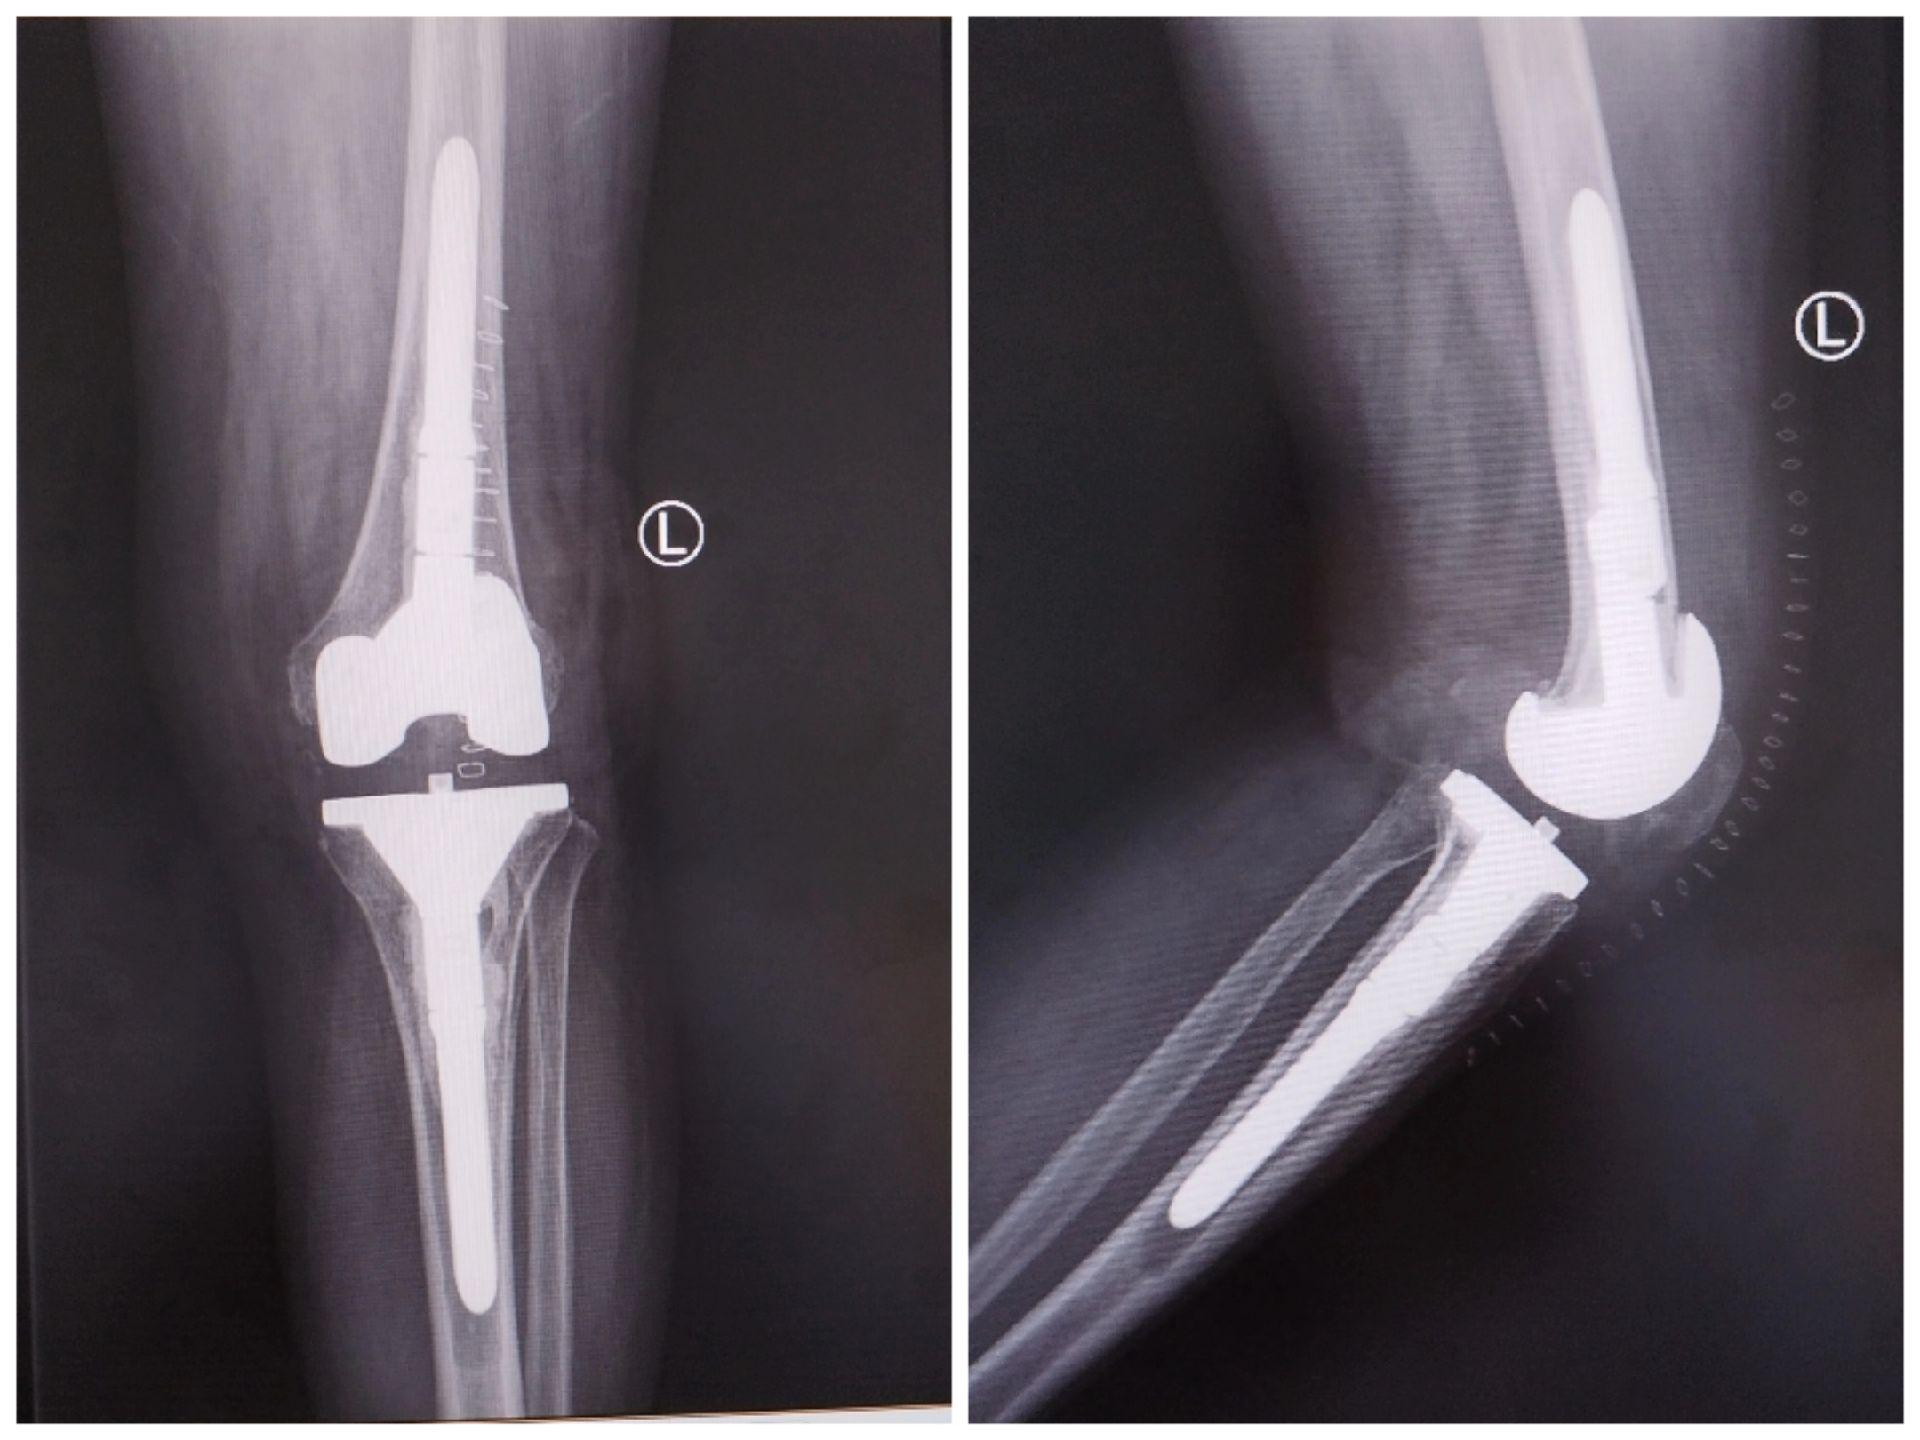

膝关节翻修术。双膝关节置换术后布氏杆菌感染(外院),清创旷置后二期翻修,重新走出自信的步伐。膝关节翻修